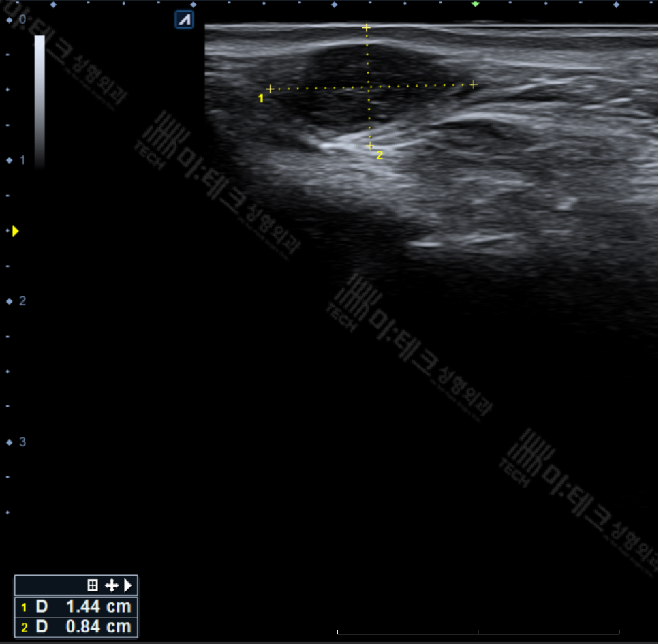

전형적인 모양은 아니지만 1.5cm가량의

피지낭종 유사 덩어리가 관찰됩니다.

모든 피지낭종이 다 같은

초음파 모양을 띄고 있지는 않거든요.